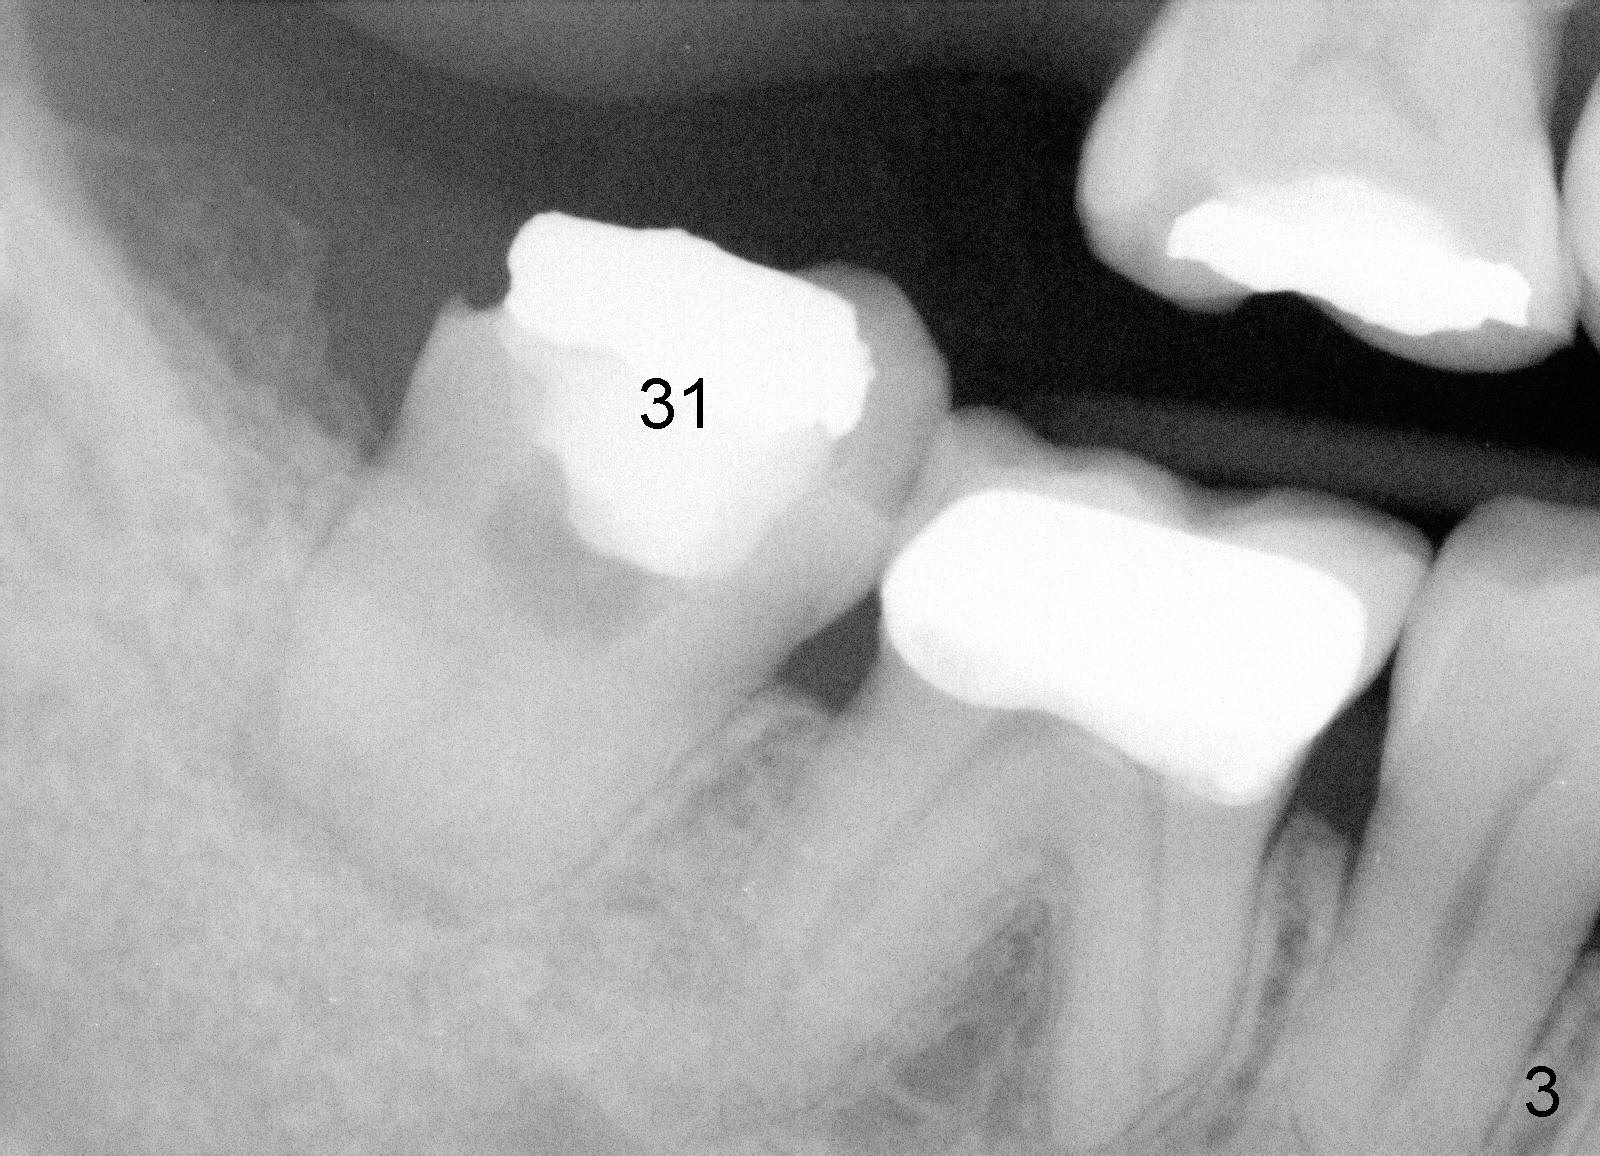

A 43-year-old lady develops tinnitus recently. Her primary care physician suspects that it is related to root canal therapy for the teeth #18 and 19 (Fig.1). Several more treatment is needed: extraction of #16 (Fig.1), RCT of #31 (Fig.1,3) and implant for #2 (Fig.1,2). Sinus lift and probably bone expansion may be required for #2 implant placement. Does usage of osteotomes worsen tinnitus, similar to occasional occurrence of vertigo after bone expansion?